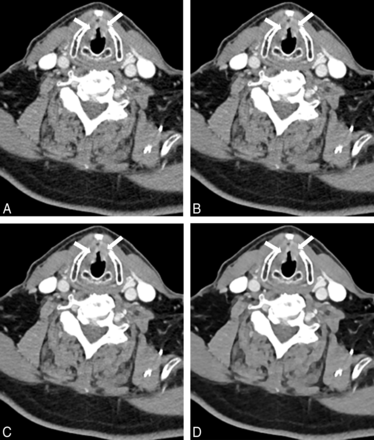

Sternocleidomastoid muscle–fat CNR was significantly higher in ADMIRE 3 and 5 compared with FBP and ADMIRE 1, with the highest CNR in ADMIRE 5 (all, P < .001). Sternocleidomastoid muscle–fat CNR in FBP was slightly higher than that in ADMIRE 1 (P = .256). Submandibular gland–fat CNR was highest in ADMIRE 5 compared with FBP and ADMIRE 1 and 3 (P < .001). Submandibular gland–fat CNR in FBP was nonsignificantly higher compared with ADMIRE 1 (P = .430) but was significantly lower compared with ADMIRE 3 (P = .004). Internal jugular vein–sternocleidomastoid CNR was significantly higher in all ADMIRE strength levels compared with FBP, with the highest CNR in ADMIRE 5 and significant differences within the ADMIRE strength levels (all, P < .001). Results of CNR calculations are summarized in Table 2, and comparisons of CNR calculations are shown in Fig 3. Figure 4 shows axial images of a bilateral T2 glottic larynx cancer by using FBP and ADMIRE 1, 3, and 5.

Images of a 46-year-old male patient examined with a low tube voltage of 90 kV on 192-section DSCT (window settings: width, 400 HU; level, 80 HU). Images were reconstructed by using filtered back-projection (A) and advanced modeled iterative reconstruction with strength levels 1 (B), 3 (C), and 5 (D). Axial images show histologically proved bilateral T2 squamous cell carcinoma of the glottic larynx (arrows). Image noise was highest by using FBP (A). The higher ADMIRE strength levels show consistently lower image noise (B–D). The internal jugular vein–sternocleidomastoid muscle CNR is highest by using ADMIRE 5 (D). Delineation of smaller structures was considered good by both observers in all images.